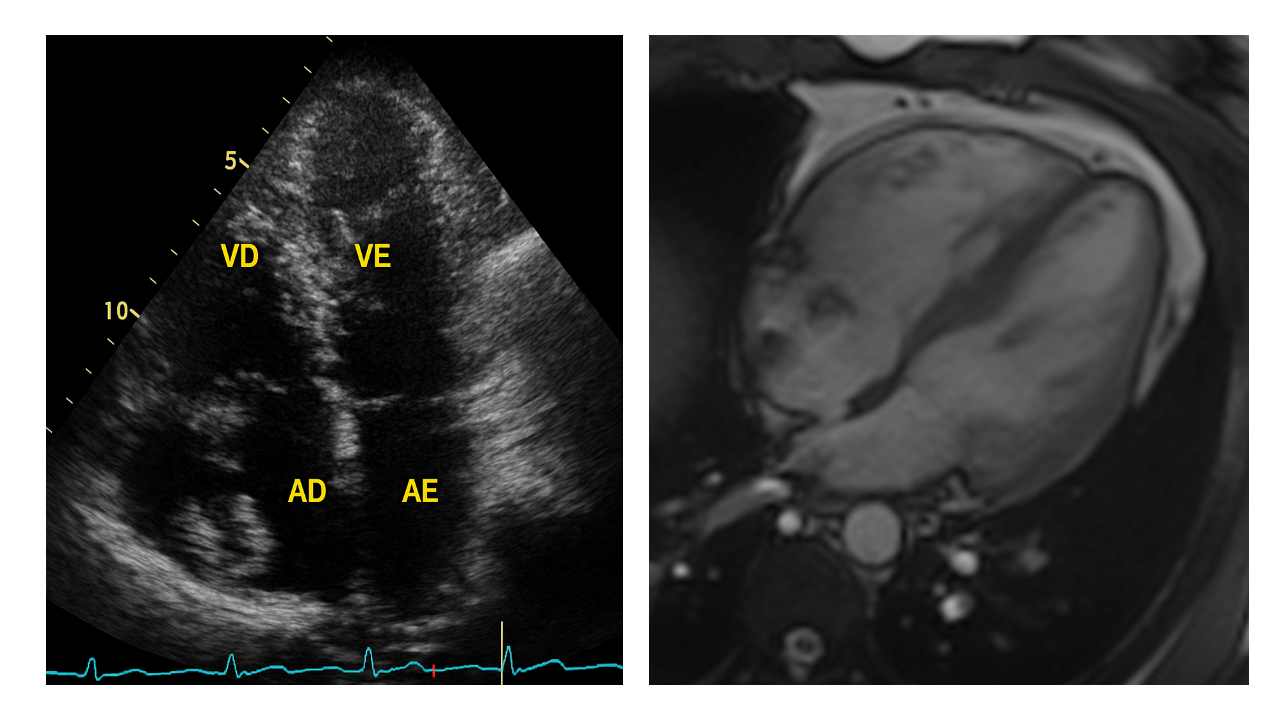

Image 1: Transthoracic echocardiography and cardiac magnetic resonance bSSFP four-chamber view demonstrate a well-delineated intracavitary structure located within the RA, located in close proximity to the tricuspid annulus. Cavity dimensions are preserved.